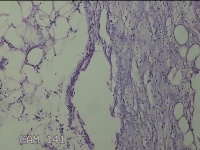

性别

男

年龄

56岁

临床诊断

右侧腋下结节

一般病史

标本名称

大体所见

灰白粉红色组织2.3x2x0.8cm一块,表面带梭形皮肤2.3x2cm,皮下见结节2x1cm一个,结节部分已切开,见结节呈囊性,囊内有少许灰白色角化物,囊壁厚0.1cm。

炎性病变。